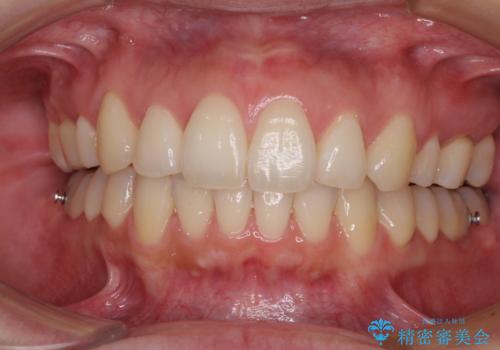

再矯正で突出した口元を引っ込める 抜歯矯正の後戻り

- 抜歯矯正の後戻りで前歯が突出してきていることを気にして来院された患者様です。

口元の突出感を改善するにあたり、抜歯矯正は行うことができないため、奥歯の後方移動とIPR(歯と歯の間を削る)により達成することとしました。

再度後戻りしたときに対応しやすいよう、インビザラインにて矯正治療を行うこととしました。

しっかりと装着時間を守り、ゴムかけにも協力していただいたので、口元を引っ込めることができました。